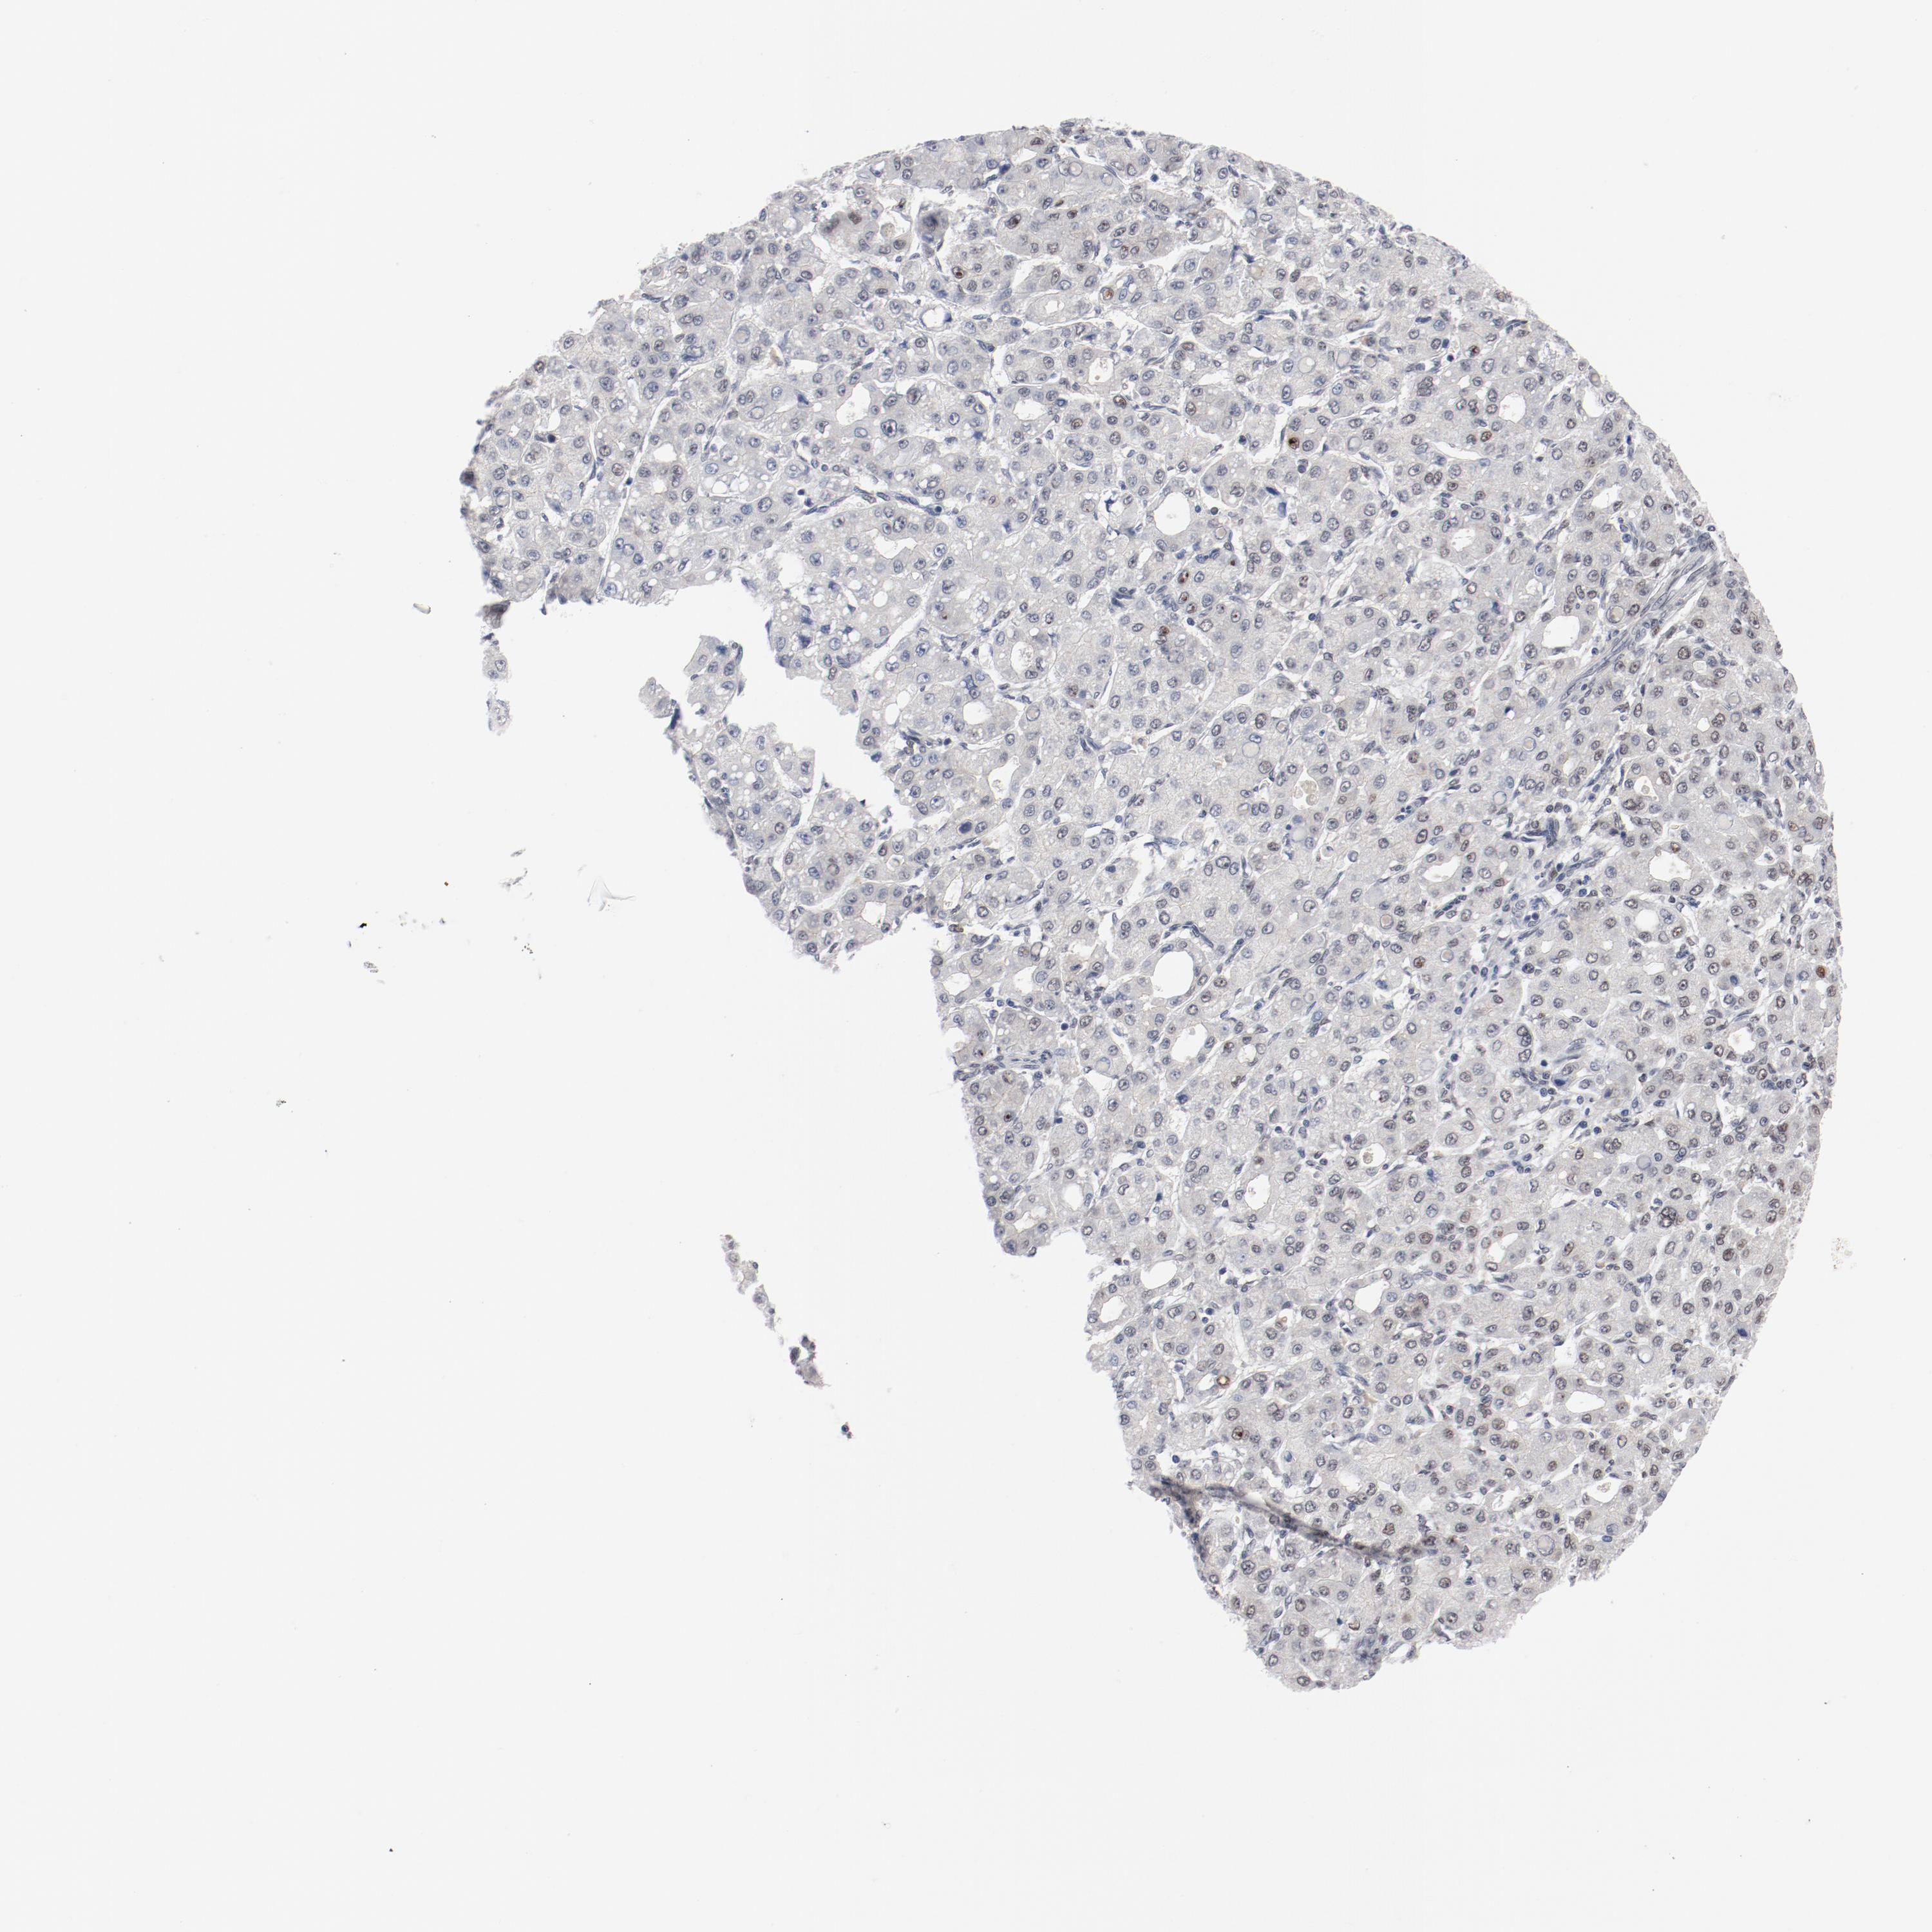

LIVER CANCER - Protein expressioni

A mouse-over function shows sample information and annotation data. Click on an image to view it in a full screen mode. Samples can be filtered based on level of antibody staining by selecting one or several of the following categories: high, medium, low and not detected. The assay and annotation is described here.

Antibody stainingi

Antibody staining in the annotated cell types in the current human tissue is reported as not detected, low, medium, or high, based on conventional immunohistochemistry profiling in selected tissues. This score is based on the combination of the staining intensity and fraction of stained cells.

Each image is clickable and will lead to virtual microscopy that enables deeper exploration of all samples and also displays staining intensity scores, fraction scores and subcellular localization as well as patient and tissue information for each sample.

Antibody HPA001759

Cholangiocarcinoma

Carcinoma, Hepatocellular, NOS